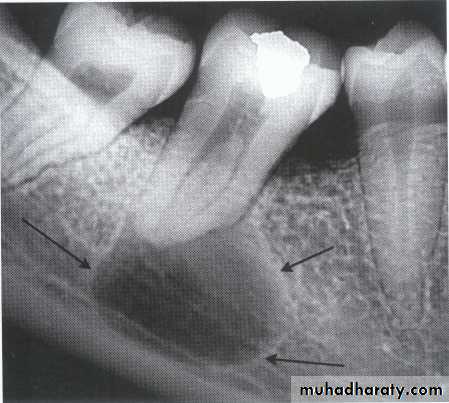

Multilocular appearance, expansion (arrowed) and considerable displacement of the adjacent teeth.

Buccal and lingual expansion (arrowed) and the undulating cortical border.

• Aneurysmal Bone Cyst

•Large multilocular aneurysmal bone cyst

in the ramus with marked expansion and

the displacement of/8.